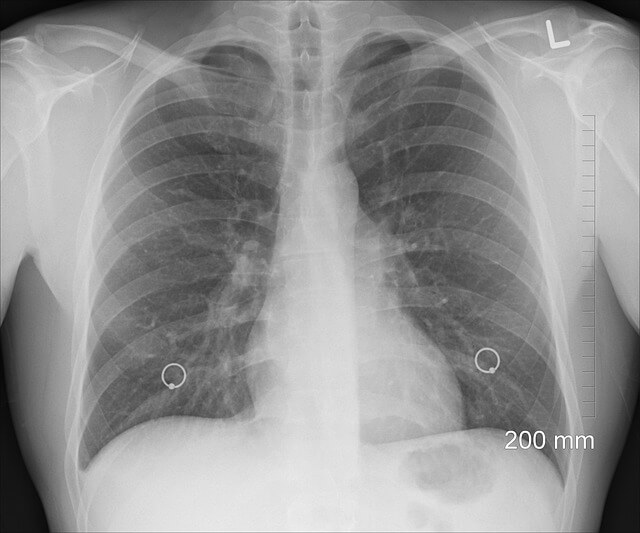

• 폐에 물이 찼을 경우 조기 치료가 필수

• 이뇨제, 산소 치료, 흉수 배액술 등의 치료법이 있음

• 흉수 배액술이 필요한 경우 전문의 상담이 필수

• 치료 후 재발 방지를 위해 저염식, 운동, 건강관리 필요